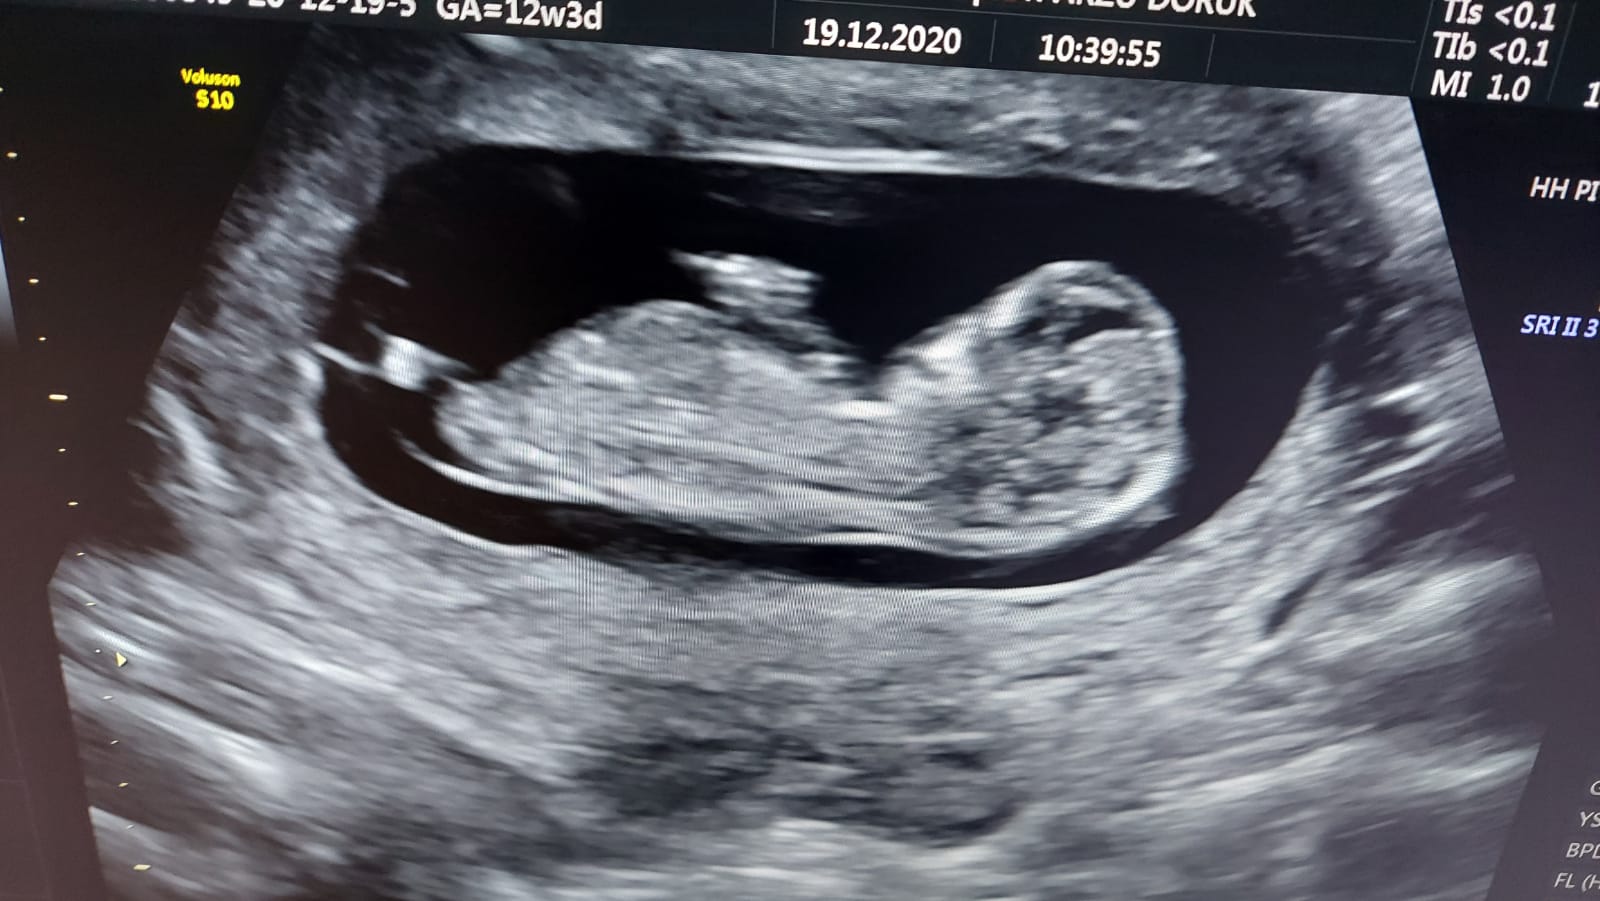

Benim bebeğime de bakar mısınız 12 hafta 3 günlük

• E1805736-55BC-4605-9939-39F2CC362BF1.jpeg

E1805736-55BC-4605-9939-39F2CC362BF1.jpeg

160,7 KB · Görüntüleme: 390